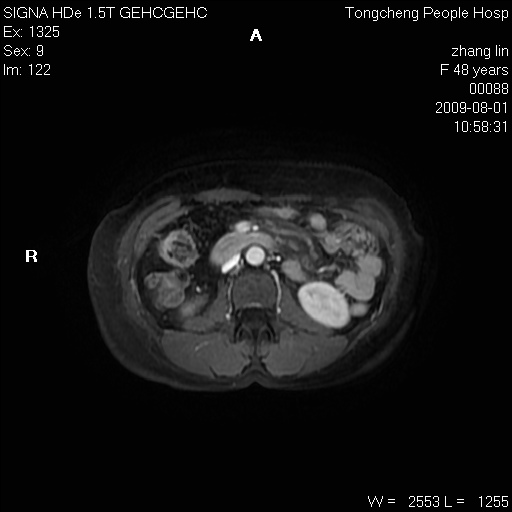

女,48岁。健康体检,彩超发现右肾占位性病变。平素健康。

临床诊断:右肾占位性病变,性质待定(囊肿?肿瘤?)。

上中腹部mr平扫+增强扫描,图像如下:

右肾上极见一类圆形病灶,t1wi呈等信号t2wi呈等高混杂信号,三期增强无强化,边界清---考虑囊肿出血。

同反相位均表现为等信号,病变无强化,考虑含蛋白的囊肿可能,弥散加权相或许有些帮助,

肝囊肿

慢性胆囊炎